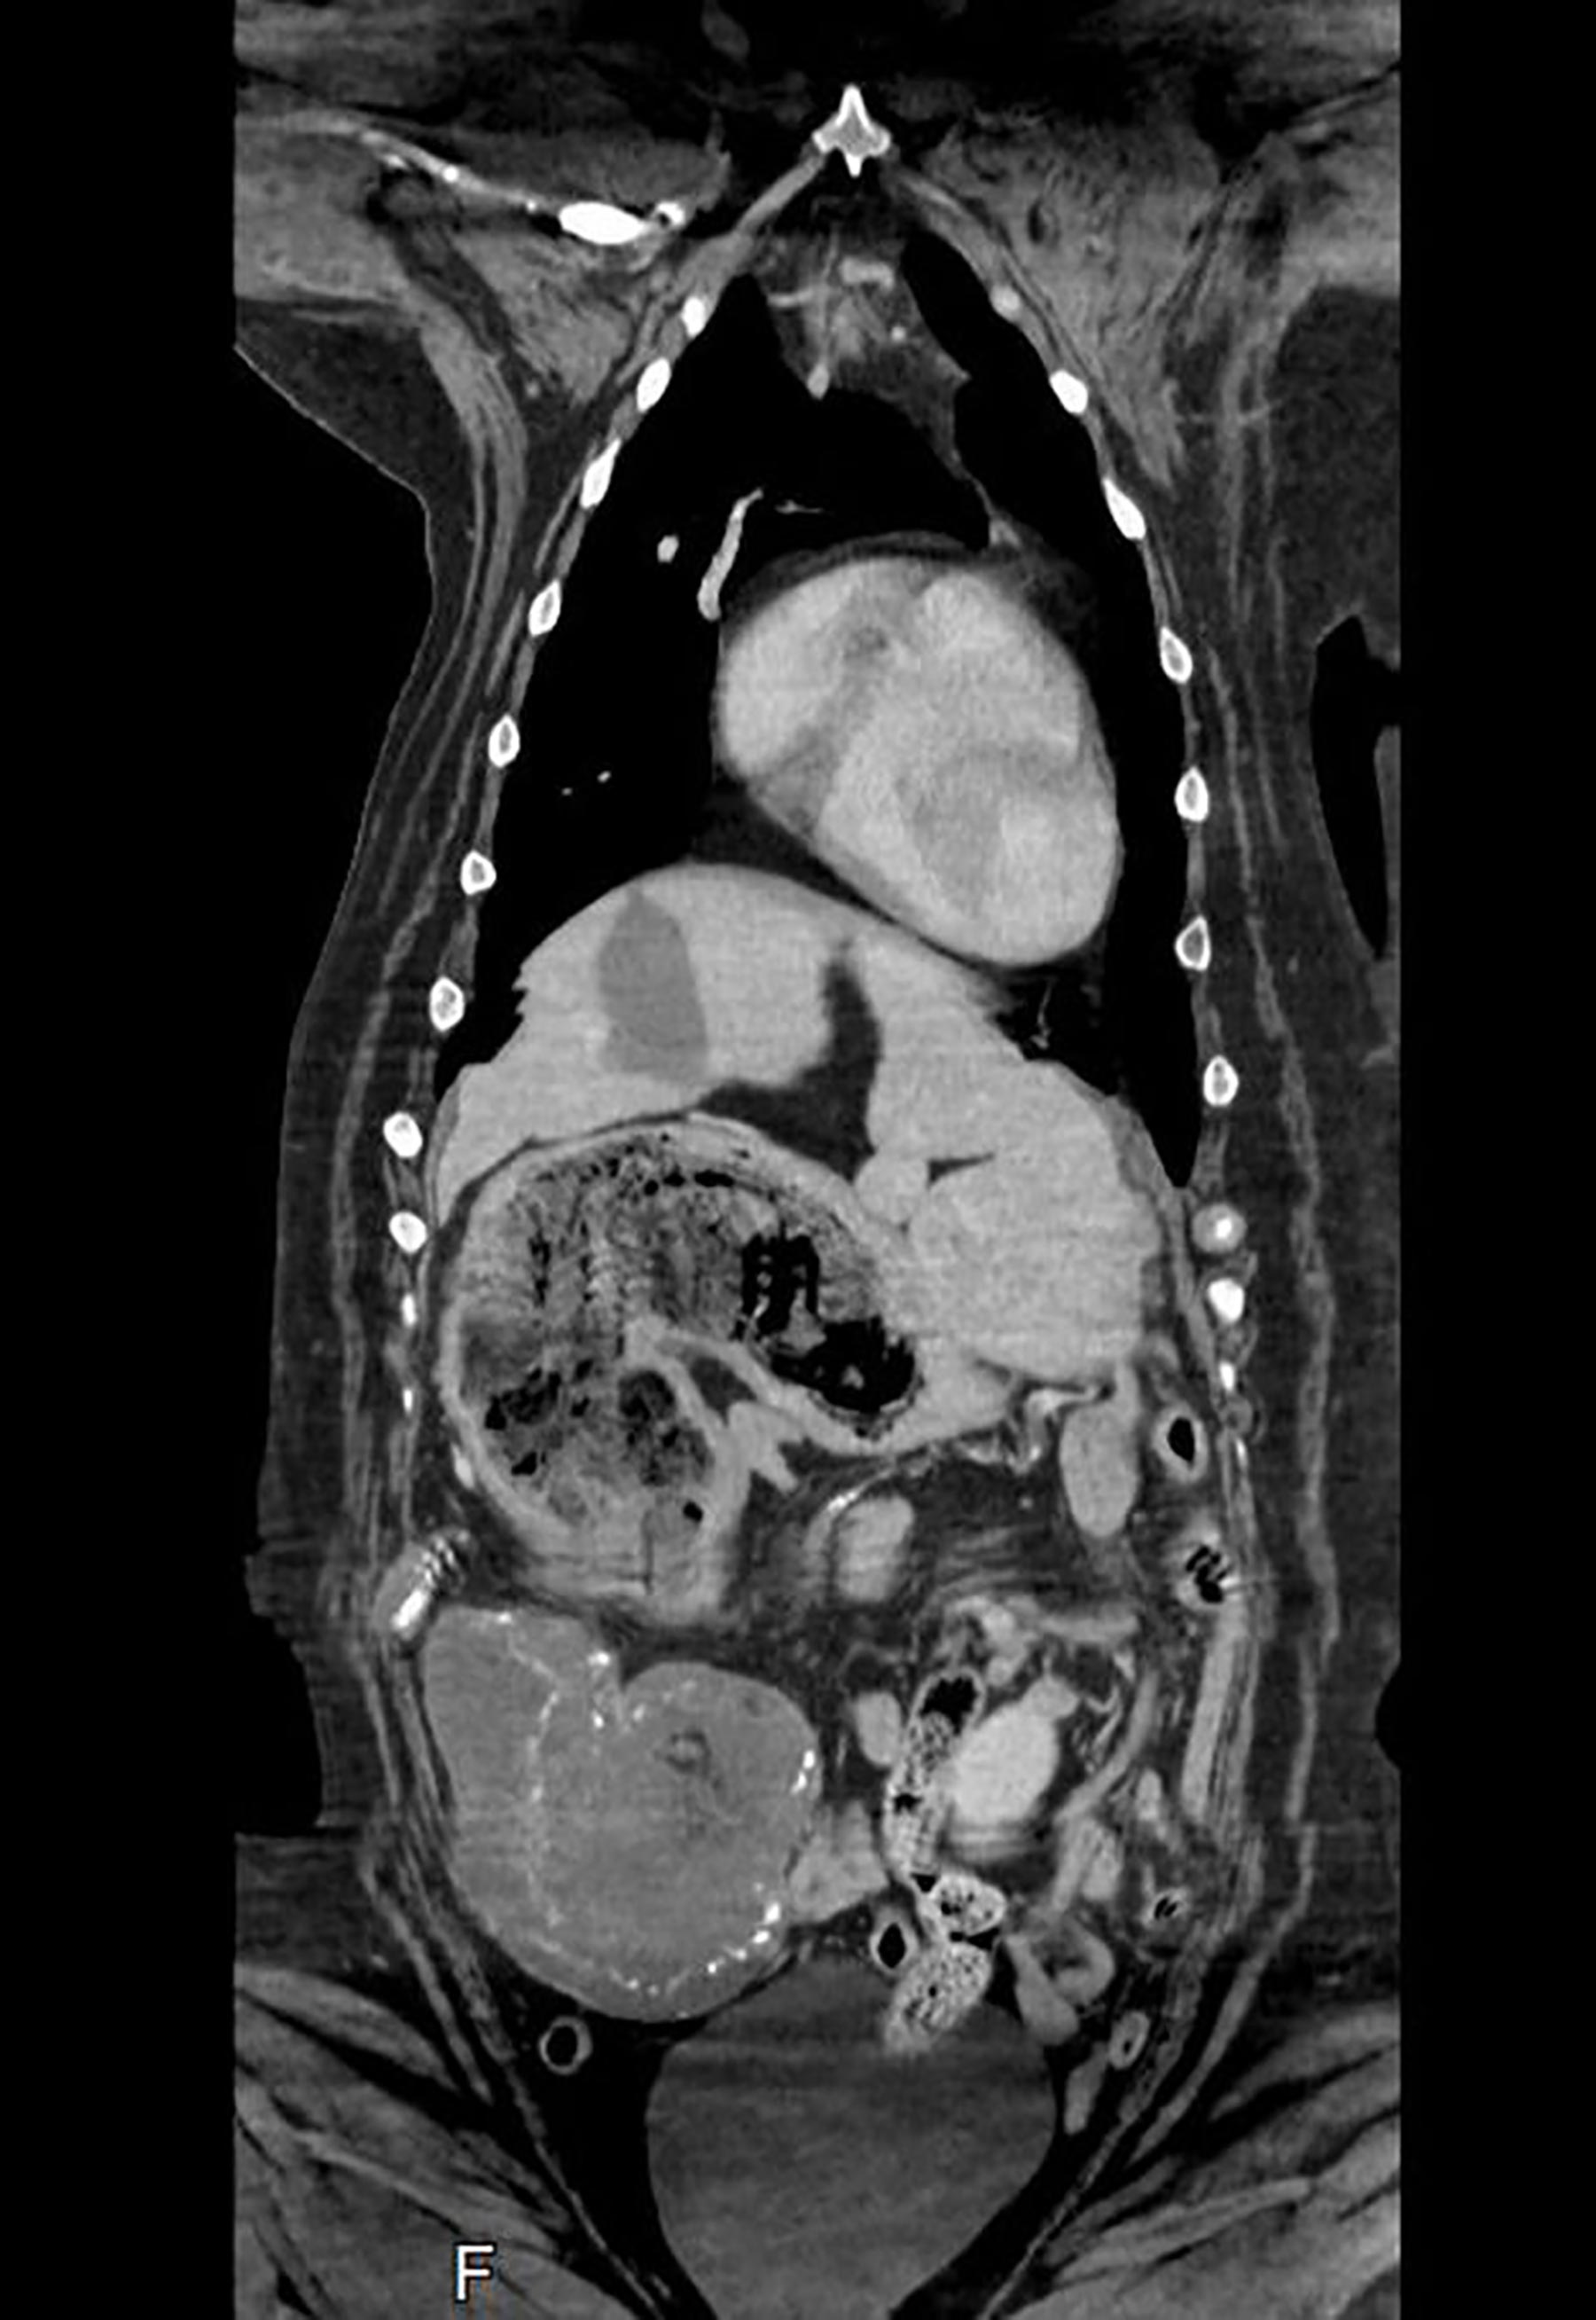

Maisy was given a CT scan by Wakefield-based vet Nick Blackburn of Paragon Veterinary Referrals, who saw the pup was suffering from an unusually full stomach and a mass on her spleen. This led him to make his original diagnosis, which suspected cancer.

However, during an operation to remove the dog’s spleen, the vet discovered the plush toys in her stomach.